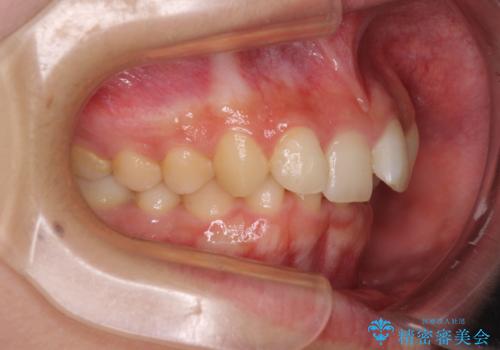

- 下顎前歯が欠損しており、前歯がデコボコとなっている歯並びを気にして来院された患者様です。

下顎の左右側切歯2本が欠損しており、上顎歯列がデコボコとなっている状態でした。

下顎歯列に対して上顎歯列が相対的に大きくなっているため、デコボコとなっているだけでなく、下顎前歯が見えなくなるくらいのディープバイトにもなっていました。

上顎左右第一小臼歯2本を抜歯し、ワイヤー装置にて矯正治療を行うこととしました。